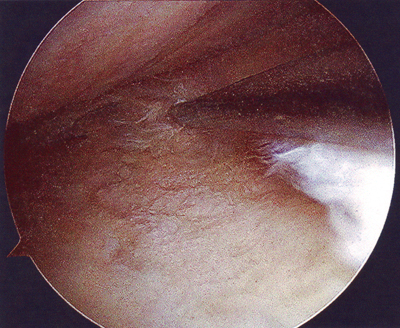

Aina jotain hyvääkin löytyy. Tässä on kuva ehjästä eturistisiteestä, joten hyvillä mielin potkitaan tästä eteenpäin!